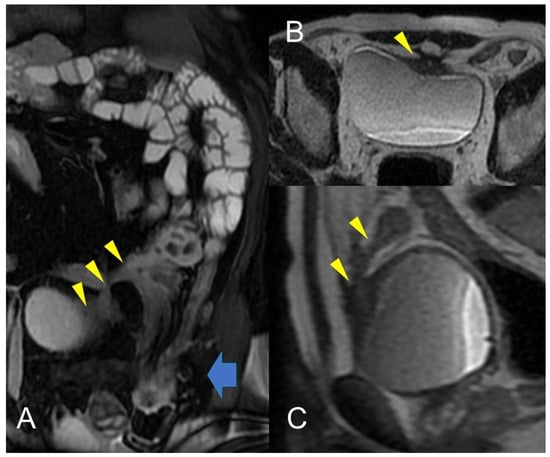

Figure 11.

Crohn’s disease is a common cause of Enterovesical fistula formation. The enterovesical fistula represents an abnormal connection between the enteric lumen and the bladder. Coronal fast imaging employing steady-state acquisition (FIESTA) images (A) show a complex fistula with one arm consisting of an enterovesical fistula (yellow arrowheads). Axial (B) and sagittal (C) T2-weighted MRE image of the same patient shows enterovesical fistula. In (A), inguinal hernia indicated by the blue arrow with involvement of a pathological section of the small intestine.